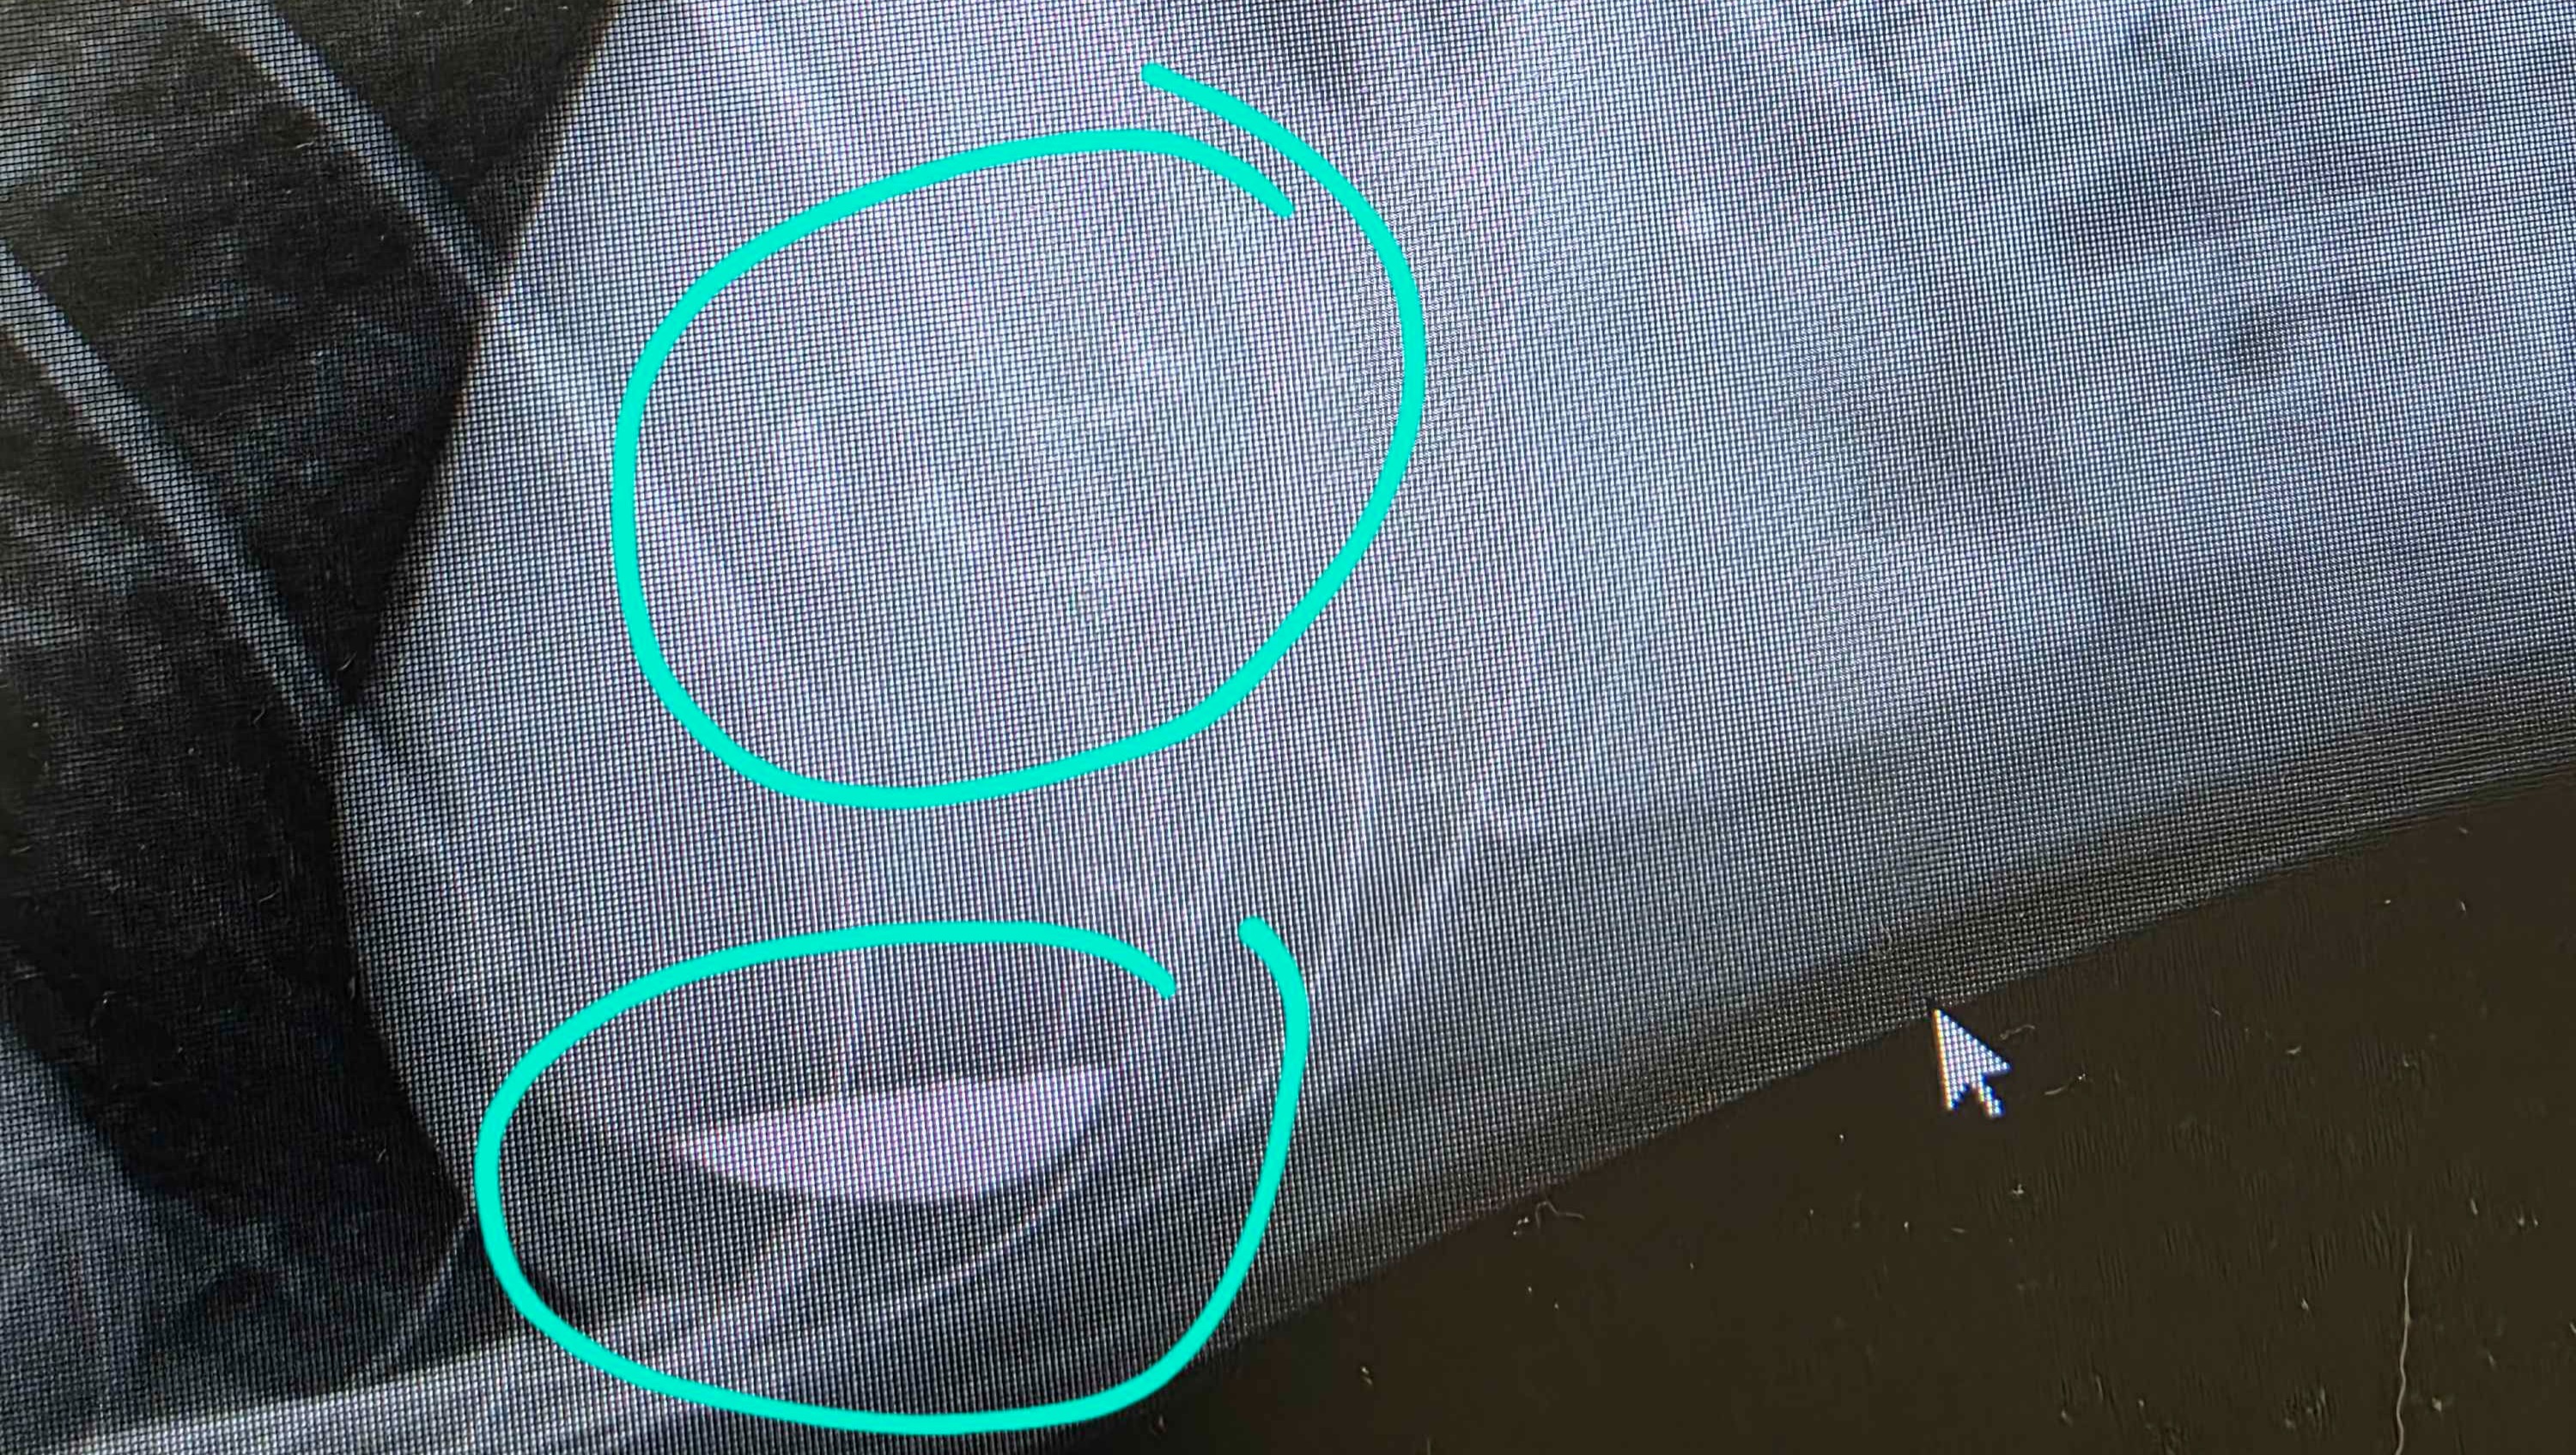

Murray's ducts, including main bile duct, were partially blocked in several places with gall stones. It took a few days to determine if they could be broken up with medicine or if he required surgery. The first option would have necessitated daily pills and monthly scans to see if more stones were forming, and it turns out it wasn't an option anyway. The only option was surgery to remove the blockages and his gall bladder to ensure that no further stones formed over time.